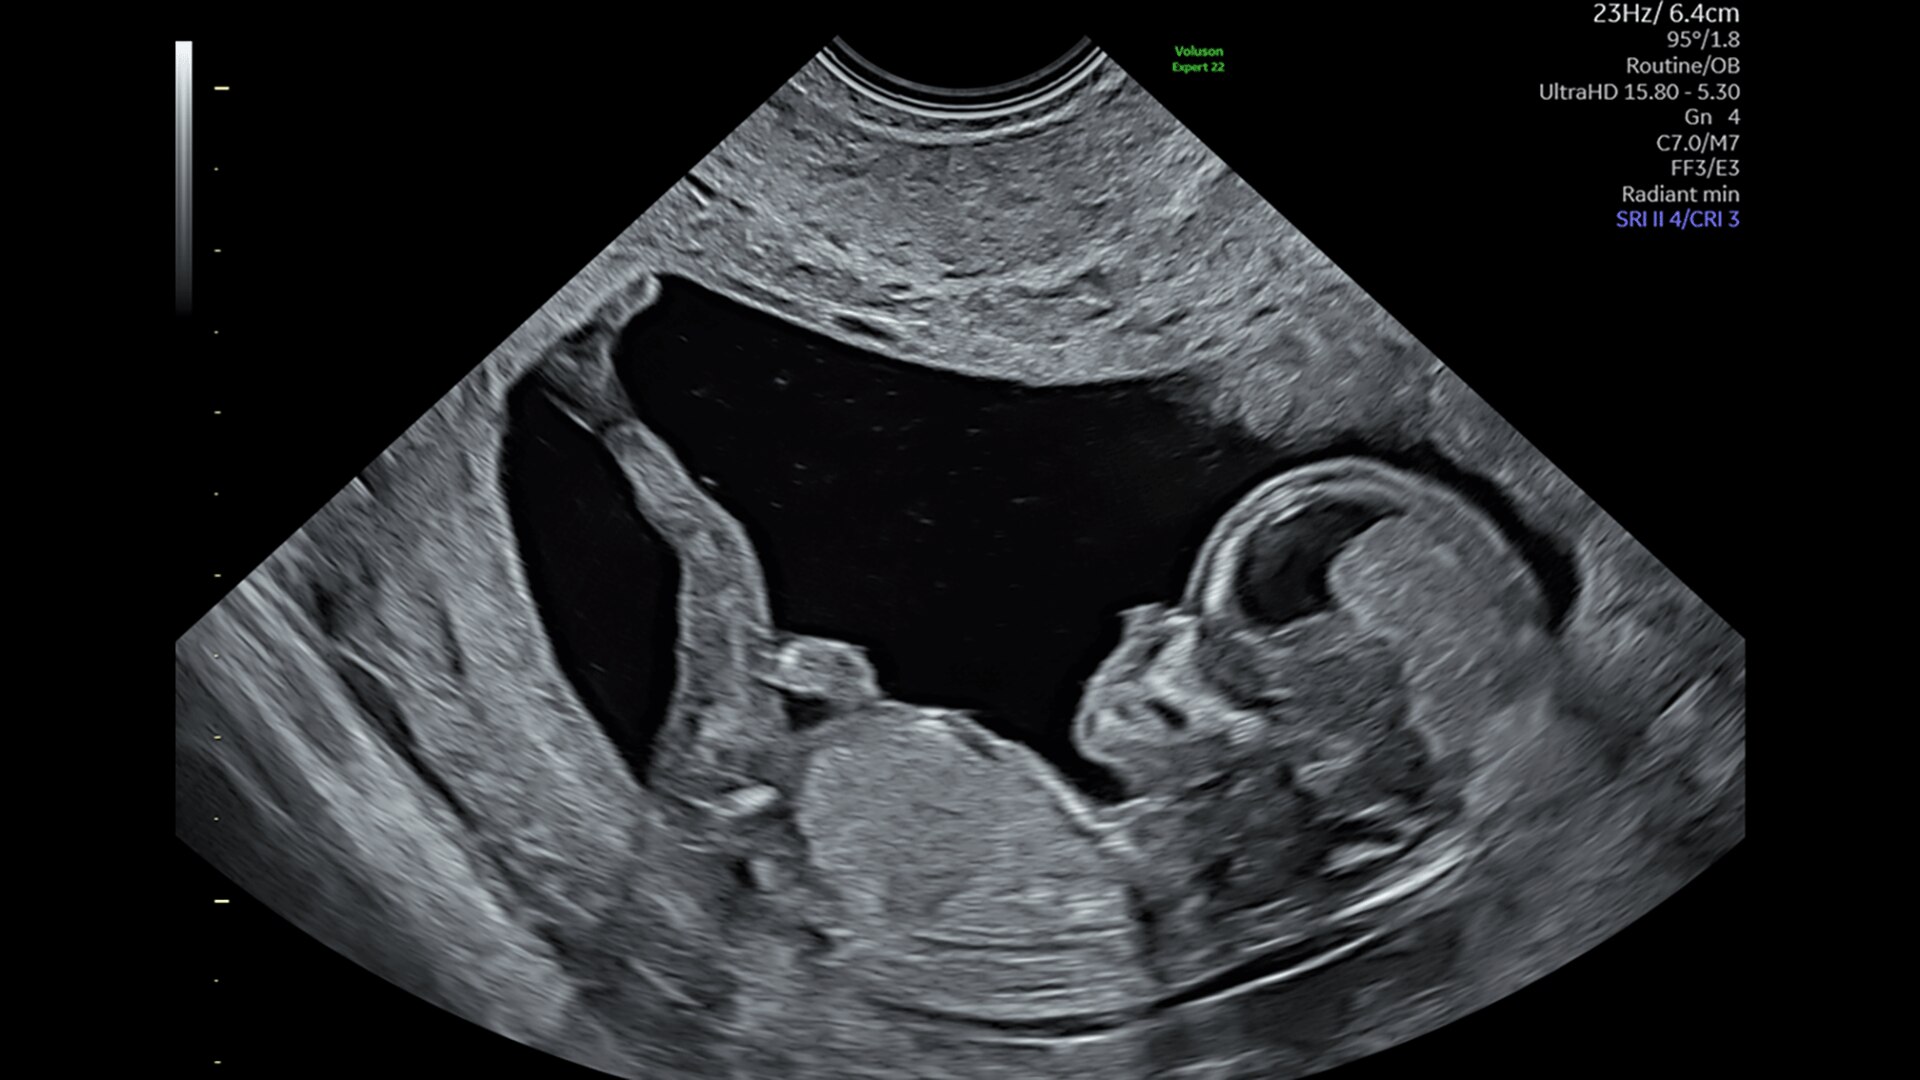

Fetal Heart Assessment

Detect, diagnose, and monitor with confidence using Radiant and fetal HQ

FETAL HEART EVALUATION

Get to the Heart of the Matter

Identifying fetal cardiac abnormalities earlier means you can intervene sooner, plan for delivery, and potentially improve outcomes. The Voluson Expert 22 provides a full solution of progressive tools, to help distinguish the tiniest structures with stunning clarity to provide patient answers faster.